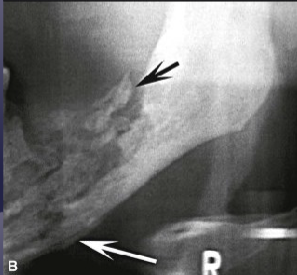

what is the black arrow pointing to

large sequestra caused by acute osteomyelitis

what is the white arrow pointing to

periosteal reaction due to acute osteomyelitis